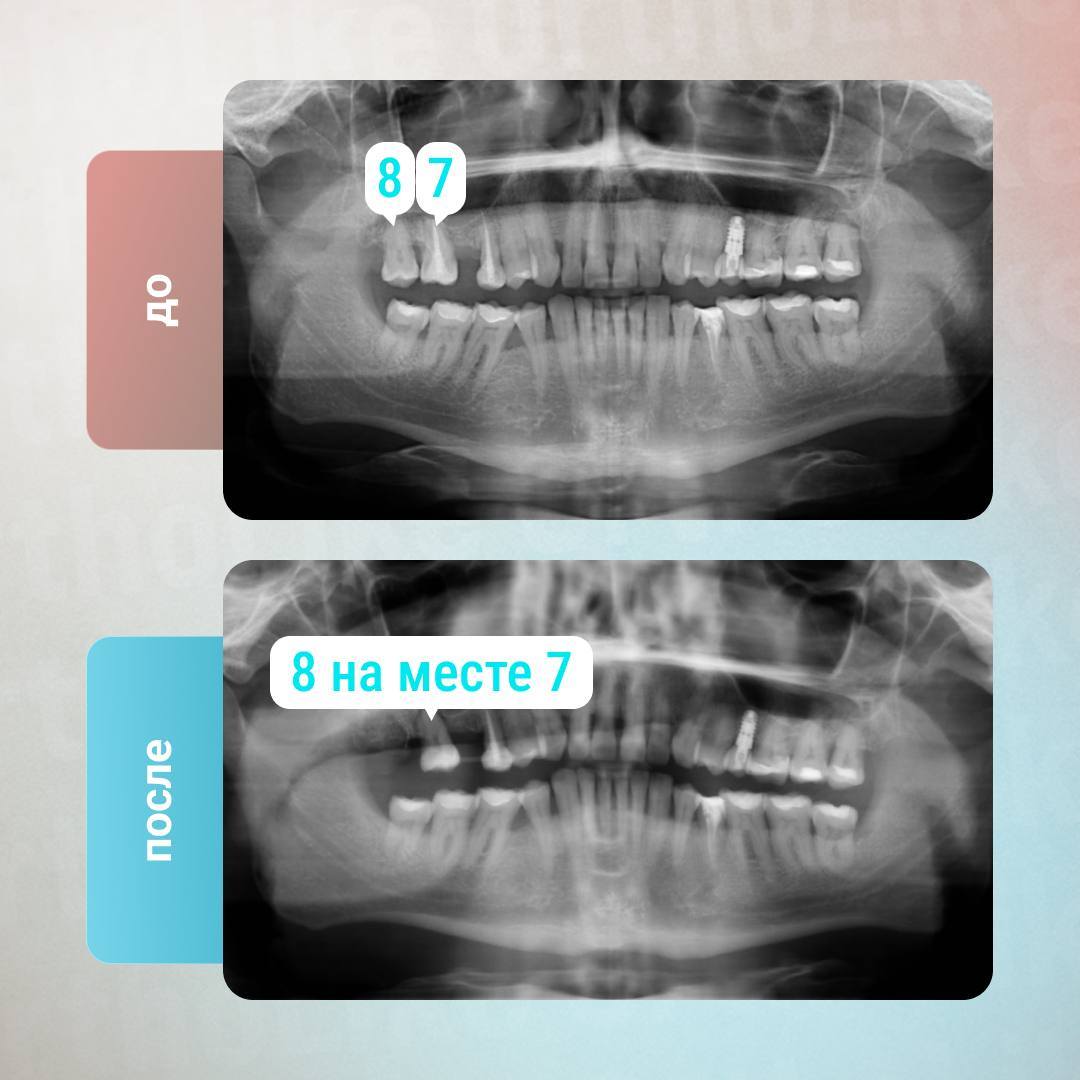

На примере реального клинического случая хирурга клиники OrthoLike видно как состоятельный зуб мудрости использовали в качестве донора для несостоятельной семерки. Это позволило сохранить целостность и анатомически правильную форму зубной дуги, жевательные функции и нормальную речь. А также существенно сократить процесс лечения и восстановления.